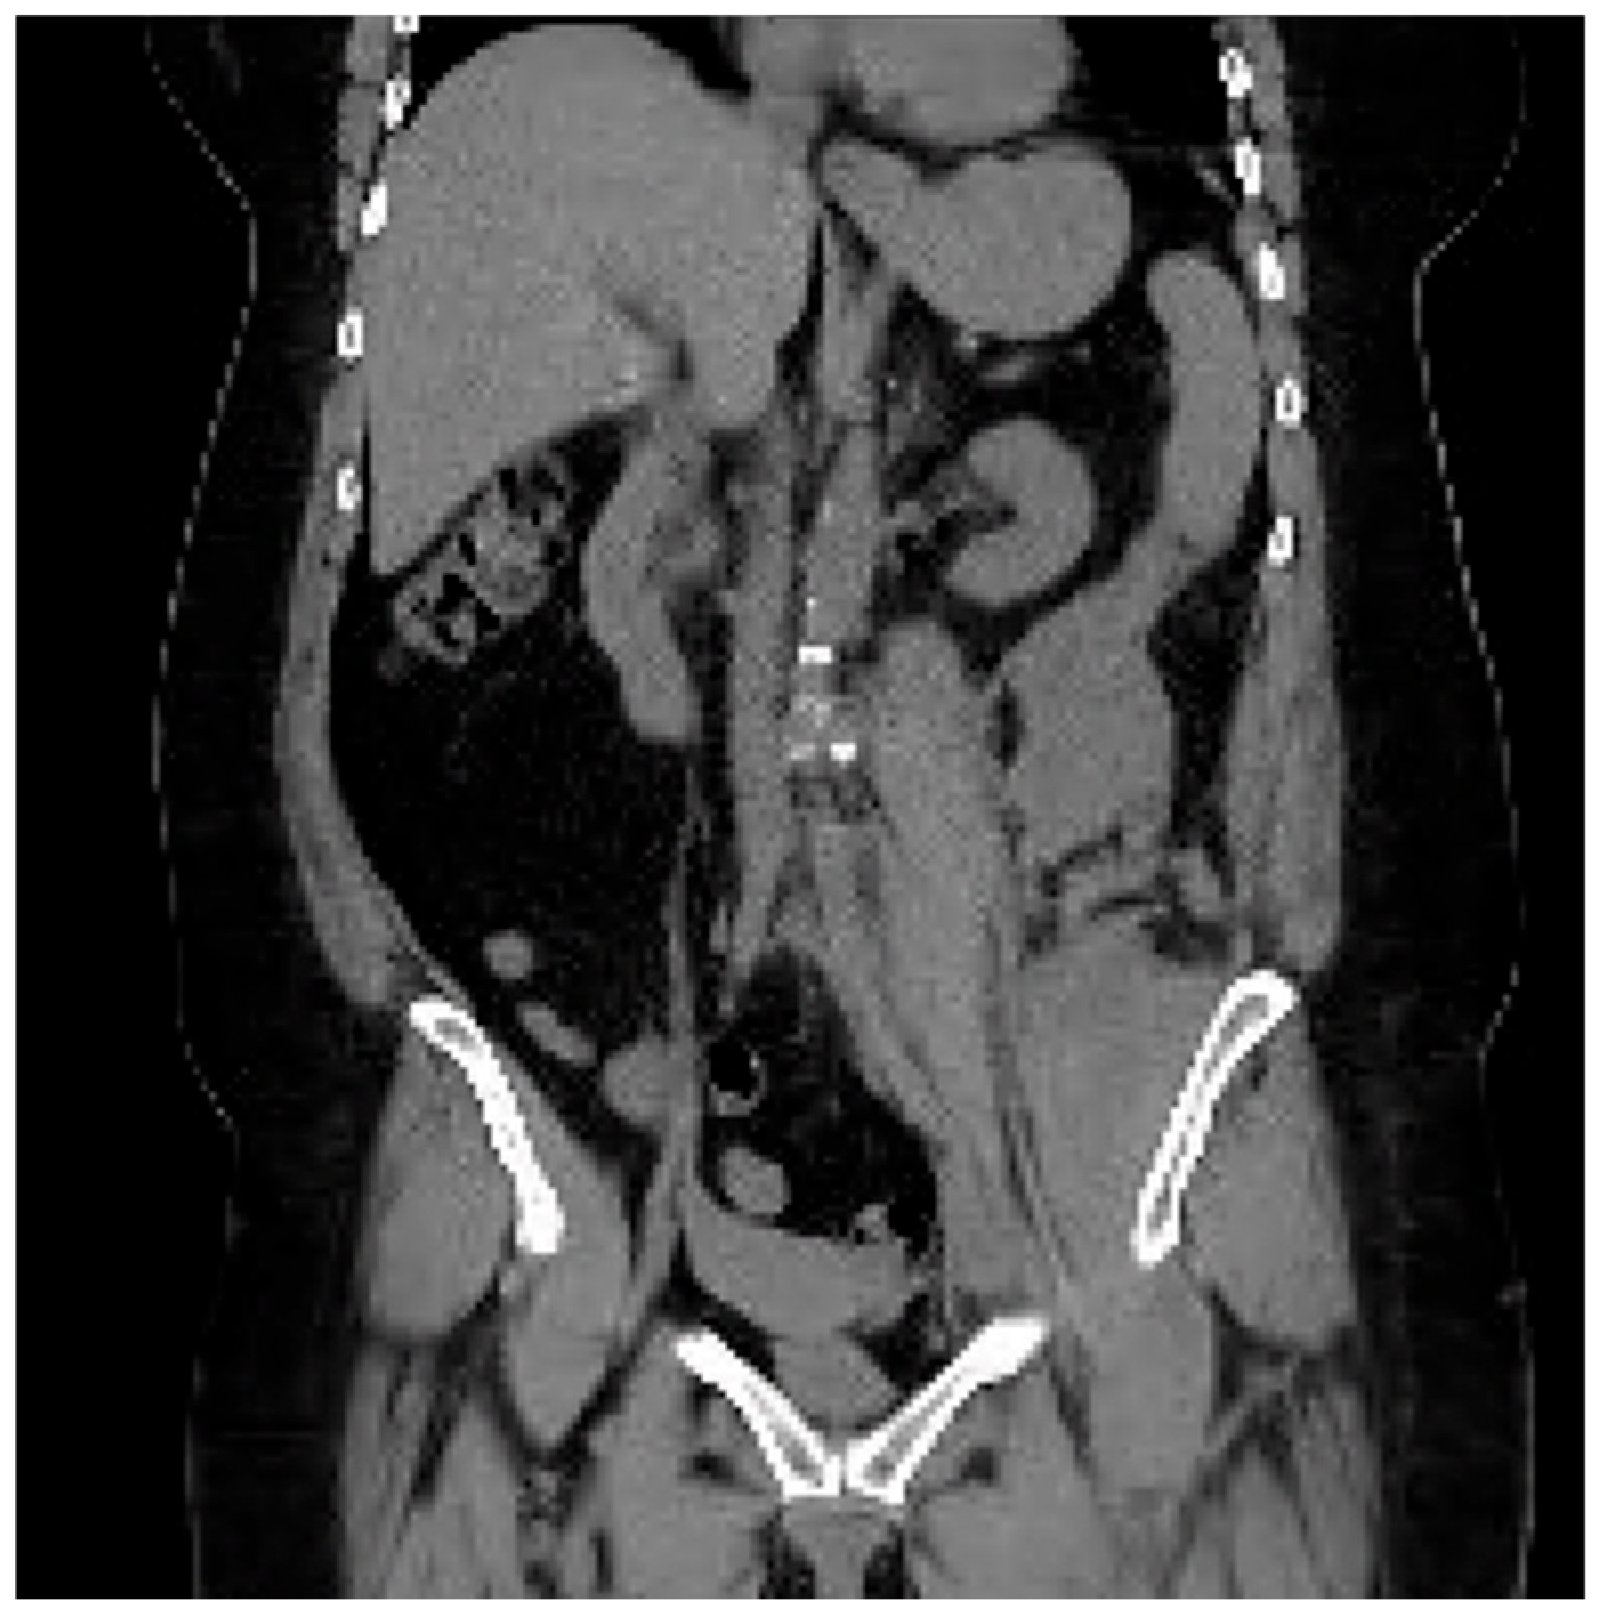

The CTA protocol images featured below (Figure 5 and Figure 6) demonstrate the retroperitoneal bleed noted on treatment day #2. This complication self-resolved without surgical or interventional radiological intervention. The patient required a total of 2 units of packed red blood cells.

Figure 4. CTA in coronal view post-tPA.

The patient was admitted to the ICU for monitoring. On day 2, she began to experience abdominal and flank pain. A repeat CT angiogram of the abdominal aorta and bilateral iliofemoral runoff showed complete resolution of the aortic and bilateral common iliac occlusion; however, the patient had a new retroperitoneal bleed. The heparin drip was stopped, and the patient required a transfusion of 2 units of packed red blood cells for blood-loss anemia. The patient’s hemoglobin levels stabilized without further intervention (and did not require any direct surgical or interventional radiology treatment). The patient ultimately had a full return of function of her lower extremities and was discharged, walking, from the hospital on day 6. Further anticoagulation was deferred due to the patient’s recent retroperitoneal bleed. At her 2-week follow-up appointment, she was noted to be ambulatory, without any neurodeficit.